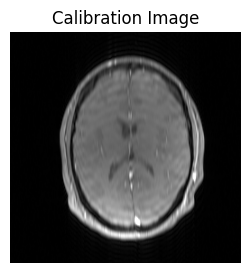

If we look at the reconstructed image, we see it is low resolution..

show_images(idat_calib_lines.rss().squeeze(), titles=['Calibration Image'])

../_images/4f7977f00b79f468a21631ed6ea6c1a0896614d2930897df7b936f0308ccc175.png

..but it is good enough to calculate coil sensitivity maps: